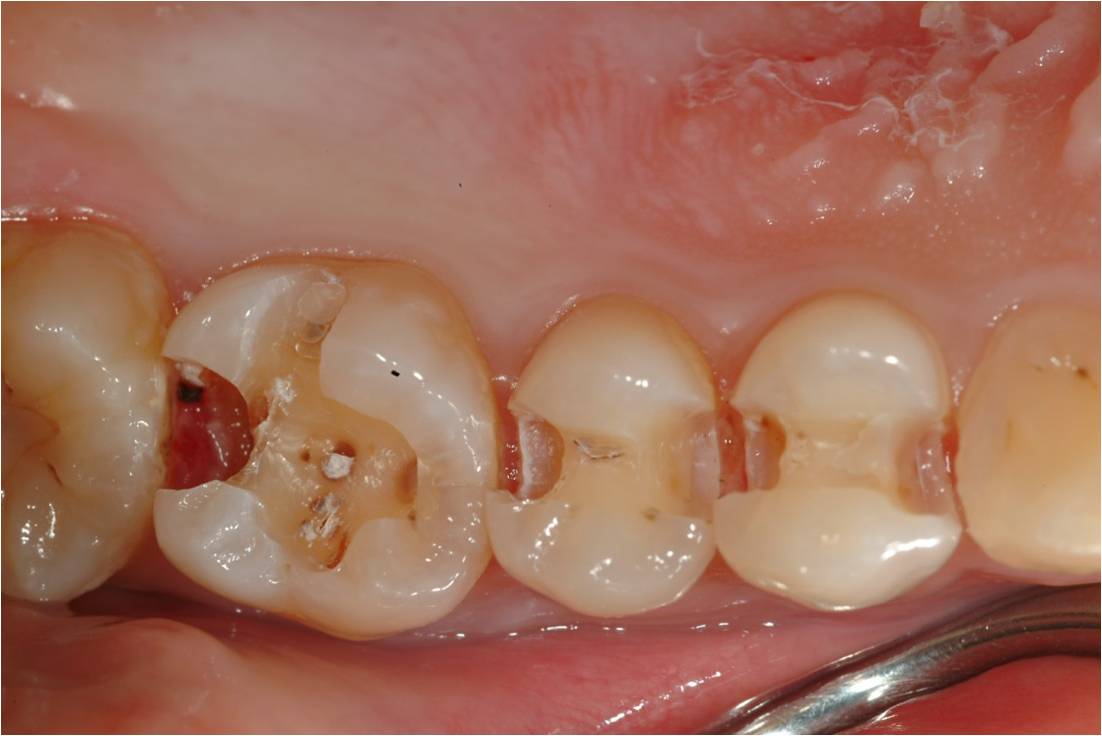

治療前,鄰接面二次蛀牙